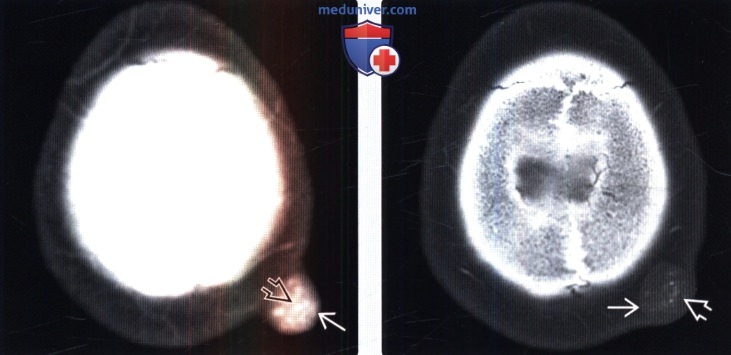

Код мкб 10 атерома головы

Код мкб 10 атерома головы 109 фото